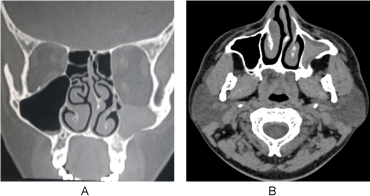

He was under regular follow up and after 4 months post-surgery, he had a well ventilated and normal maxillary sinus mucosa (Figure 4).

Figure 4: Well ventilated and healthy maxillary sinus seen through the antrostomy, 4 months postoperatively. View Figure 4